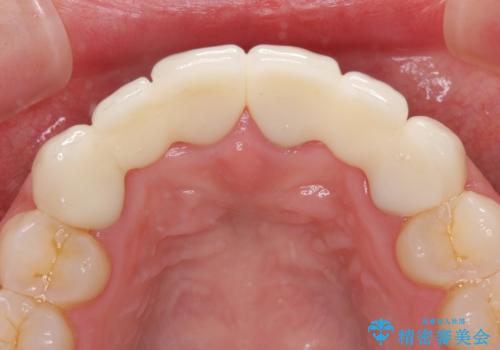

矯正治療後に前歯をセラミックブリッジに、奥の銀歯はセラミックインレーやPGAインレー(ゴールドインレー)にて補綴・修復治療を行うこととしました。

矯正治療により下顎前歯を整列させたため、上顎前歯のセラミックブリッジを補綴することで口元を少し下げることができました。